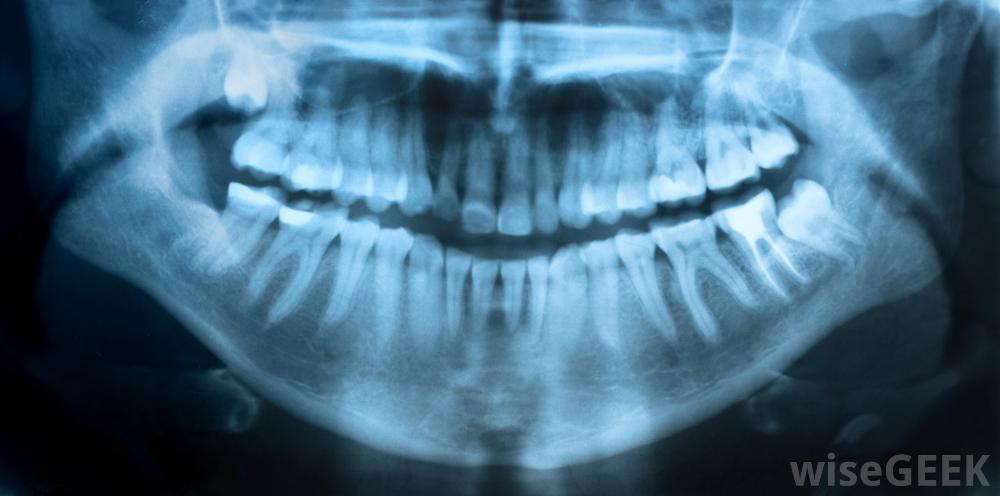

牙髓炎是指牙齒內部組織的炎癥,稱為牙髓。這種情況可分為可逆性或不可逆性兩種,治療方案也可根據這一分類而有所不同。通常,細菌可能是牙髓炎癥的原因,但有時,它可能與其他原因有關,如口腔外傷。感染和其他誘因可導致免疫系統反應,導致牙髓腫脹并壓迫牙齒的外琺瑯質。有時,牙齒中神經的結構會使找到牙髓炎的確切來源變得困難,因為疼痛會從最初的位置擴散到鄰近的牙齒。一些牙齒問題是通過x光片檢測出來的細菌性蛀牙,稱為齲齒,通過牙齒外層擴散感染牙髓,通常是牙髓炎的原因,但并不總是。對感染或創傷的免疫反應通常包括更大的血液流向該區域,因此稱為淋巴細胞的白血球可以到達該部位,并且淋巴細胞和其他細胞釋放的化學物質會導致炎癥。根據腫脹的嚴重程度,可能會引起不同程度的疼痛。在某些情況下,患有這種情況的人可能不會有任何疼痛,但在另一些情況下,可能會感覺到與血液到達該區域時相一致的劇烈搏動疼痛,同時對溫度有更高的敏感性在美國,飲用水中含氟有助于降低蛀牙的發生率。可逆性牙髓炎通常以外界刺激引起的疼痛為特征,幾次后疼痛就會消失分鐘。這種炎癥牙髓的治療通常包括消除病因。這可能是簡單的使用牙科護理產品,可以使牙齒再礦化,恢復琺瑯質的外層保護層。其他時候,可能需要抗生素來治愈潛在的感染,或者可能需要鉆孔清除受損區域,然后在現場進行填充。有些牙髓炎患者可能會出現劇烈的搏動疼痛當不可逆牙髓炎發生時,它通常會引起疼痛,在扳機被取下后,疼痛會持續10秒。像這樣無法修復的損傷有時可以通過電子手段或x光來檢測到。這種情況沒有真正的治療方法,所以通常情況下,牙髓必須為了使人得到緩解而完全拔除。有時可以進行根管切除牙髓,但在極端情況下,可能需要拔除整個牙齒牙髓炎可能是可逆的。不可逆性牙髓炎可能導致輕度疼痛和對冷熱液體的敏感性牙髓炎可以通過x射線檢測或確認。